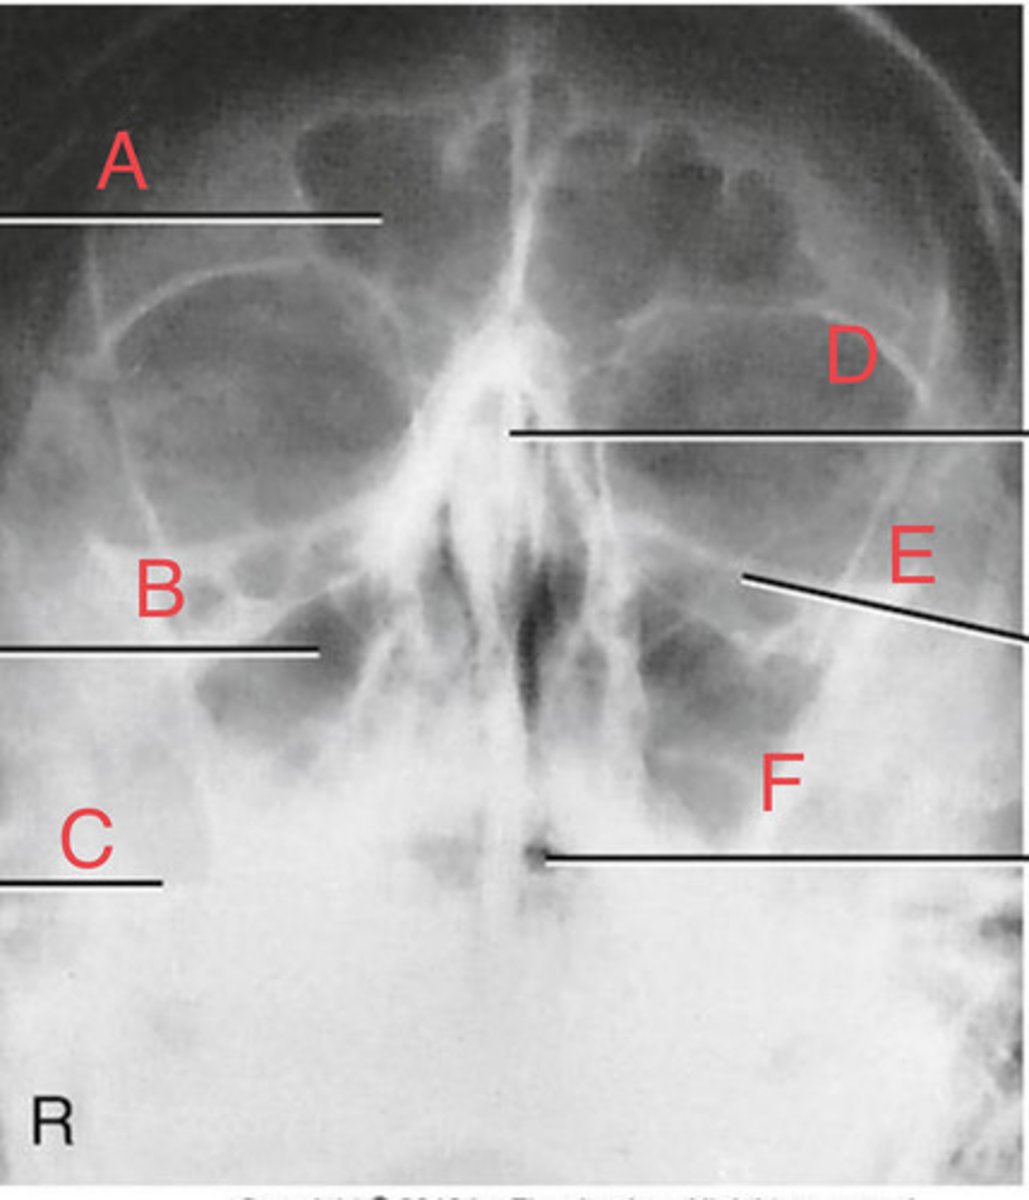

Waters sinus method

What projection?

r. frontal sinus of the frontal bone

A.

R. Maxillary sinus of maxilla

B.

R. petrous ridge of temporal bone

C.

bony nasal septum

D.

L. inferior orbital fissure of sphenoid bone

E.

Sphenoid sinus of sphenoid bone

F.

bony nasal septum

E.